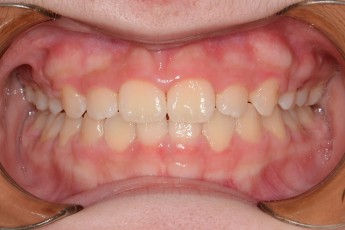

BEFORE & AFTER

- 돌출입교정